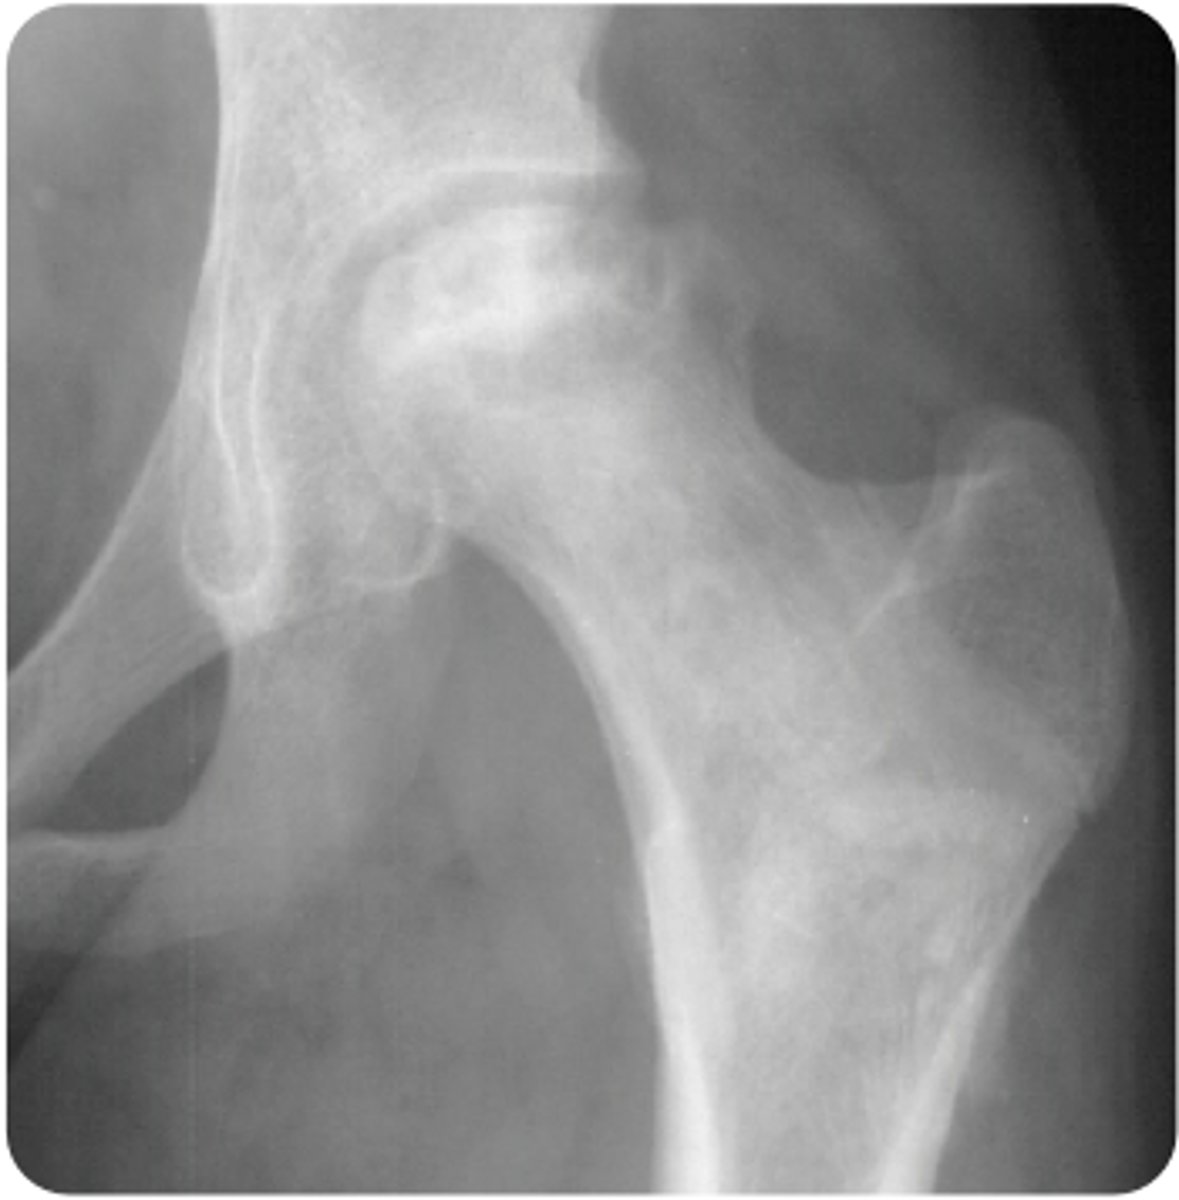

chronic glucocorticoid use

**avascular necrosis

A 17-year-old boy with a medical history significant for childhood leukemia that has been in remission for 2 years presents to the pediatrician’s office for evaluation of left hip pain. He describes the pain as constant, present at rest and at night, worse with activity, and radiating toward his groin. He states the symptoms have been ongoing for several weeks and have been steadily worsening. He is now having difficulty bearing weight on his left leg and walks with a limp. He has been taking over-the-counter ibuprofen with some relief but not a complete resolution of symptoms. He reports no specific injury or trauma, no associated fever or chills, and previous episodes of similar symptoms. He does not have radiating symptoms to his back, left knee, or right lower extremity. Vital signs are a temperature of 98.4°F, heart rate of 76 bpm, blood pressure of 116/74 mm Hg, respiratory rate of 12 breaths/min, and oxygen saturation of 99% on room air. On physical examination, he has pain with hip flexion past 90°, as well as painful and limited internal and external rotation when compared to the other side. Radiographs are shown above. What is the most likely etiology of his symptoms?

AChronic glucocorticoid use